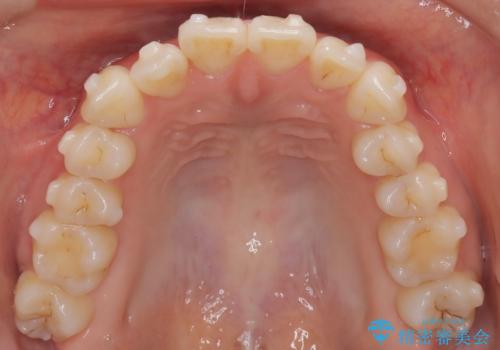

八重歯と前歯の逆の咬み合わせを、目立たない矯正で同時に改善

- 八重歯と、右上前歯(2番)が下の歯より内側に入っている反対咬合を気にされてご来院されました。精密な検査の結果、八重歯と反対咬合を同時に改善するためには、歯列全体にスペースを確保する必要があると判明。患者様のご希望から、透明で目立たないインビザライン(マウスピース矯正)による治療計画を立案しました。奥歯全体を奥へ動かす遠心移動でスペースを作り、これらの複雑な問題を一括で解消することを目指します。

今回の矯正治療では、透明なマウスピース型の装置インビザラインを使用しました。治療は、緻密なデジタル計画に基づき、奥歯から順に歯列全体を後方へ移動させる遠心移動を実施。これにより、八重歯を正しい位置に並べるためのスペースを確保しました。同時に、右上の2番を前方に誘導することで反対咬合を解消。結果として、抜歯することなく八重歯と反対咬合という複数の問題が改善され、機能的で美しい歯並びを獲得していただけました。